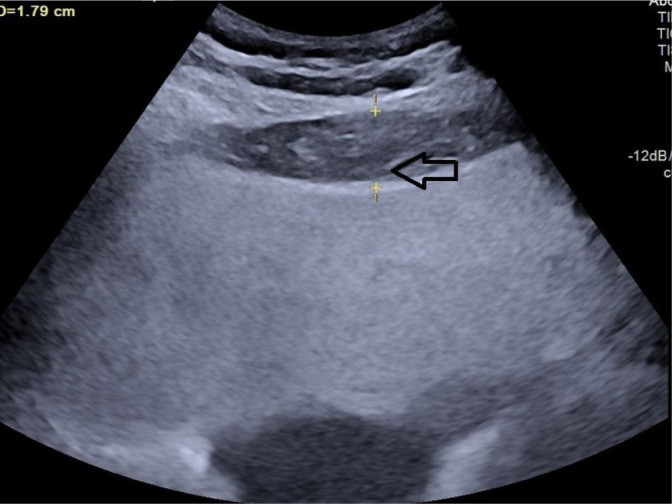

Aim: Abdominal obesity is recognized as the best predictor of cardiovascular disease risk. While body mass index has traditionally been used to measure obesity, recent evidence suggests that visceral adipose tissue may be a better indicator of cardiovascular disease risk. Various surrogate imaging markers of visceral adipose tissue have recently been described, such as posterior right perinephric fat thickness, preperitoneal fat thickness, and the abdominal wall fat index. This study aimed to examine the link between atherosclerosis through measurement of carotid intima-media thickness and markers of abdominal obesity using ultrasonography.

Material and methods: This was a hospital-based prospective observational study. Patients with a body mass index of 25-40 were included as cases and those with a body mass index 18.0-24.9 as controls. Posterior right perinephric fat thickness, preperitoneal fat thickness, and abdominal wall fat index were measured and compared with carotid intima-media thickness in cases.

Results: A total of 100 cases and 100 age- and sex-matched controls were included. Body mass index did not show any statistically significant correlations with carotid intima-media thickness in this study. Among the visceral adiposity markers, posterior right perinephric fat thickness was the most sensitive and specific predictor of carotid intima-media thickness, while the abdominal wall fat index was the least sensitive and specific.

Conclusions: Ultrasonographic markers of visceral adipose tissue, especially posterior right perinephric fat thickness and preperitoneal fat thickness, demonstrate a stronger association with carotid atherosclerosis than body mass index, making them useful predictors, particularly in individuals with high body mass index. These markers can be measured during routine abdominal ultrasounds to screen for atherosclerosis risk in patients with abdominal obesity.